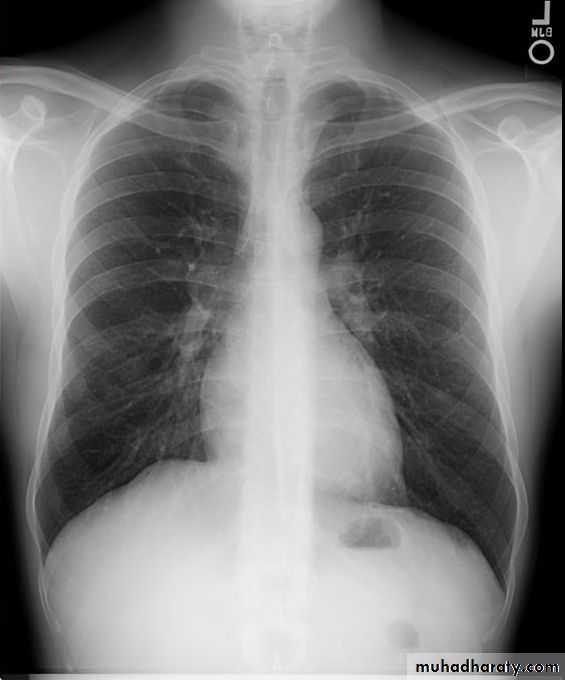

Chest X-ray; Shows bi-basal reticular nodular shadowing and asbestos-related pleural disease is usually present. HRCT scanning is more sensitive.

Pulmonary function tests; Typically show a restrictive defect with decreased lung volumes and reduced gas transfer factor.